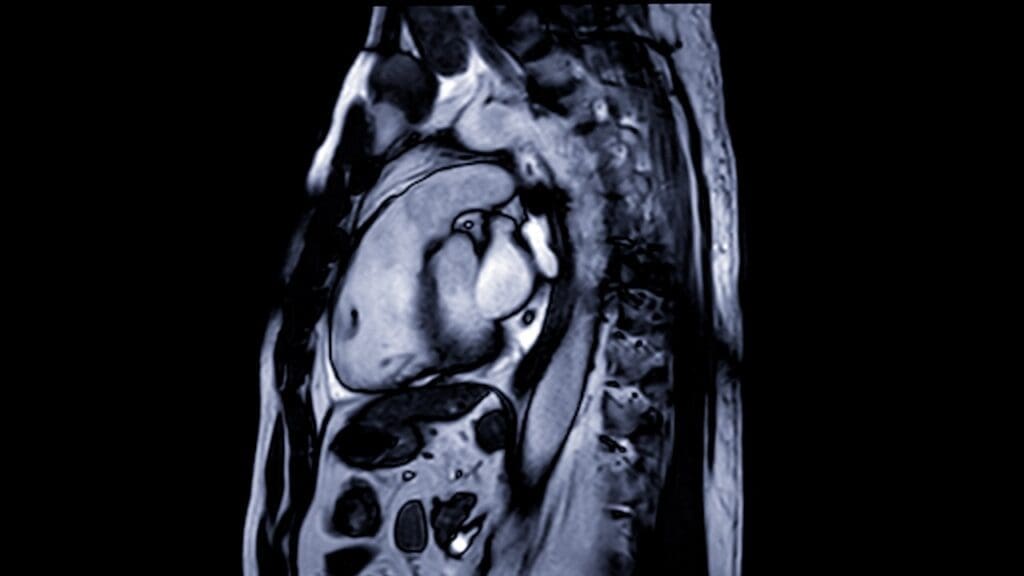

The heart is one of the most complex organs to visualize because it is located deep inside the rib cage, protected by bone structures, and constantly in motion. For this reason, examining the heart and its intricate functions requires highly advanced imaging technology and expert medical specialists. A Cardiac MRI Scan is an innovative imaging method that enables a detailed, non-invasive examination of the heart and surrounding vessels without the need for surgical procedures.

A Cardiac MRI Scan is an advanced medical imaging procedure that uses magnetic resonance technology to produce highly detailed images of the heart. Unlike conventional imaging methods that rely on X-rays or radiation, a Cardiac MRI Scan uses powerful magnetic fields and radio waves to capture clear images of the heart’s structure and function.

The major advantage of a Cardiac MRI Scan is that it provides an accurate evaluation of the heart muscle, valves, and blood vessels in three dimensions. This level of precision allows physicians to assess heart conditions with greater clarity, identifying even the smallest abnormalities. Because no ionizing radiation is involved, a Cardiac MRI is considered one of the safest diagnostic methods available for both children and adults.

The Cardiac MRI Scan captures multiple detailed images from different angles, creating a three-dimensional model of the heart. This model provides doctors with a complete view of the heart’s anatomy and function. Once the imaging is complete, the data is analyzed by radiology and cardiology specialists to prepare a detailed report.